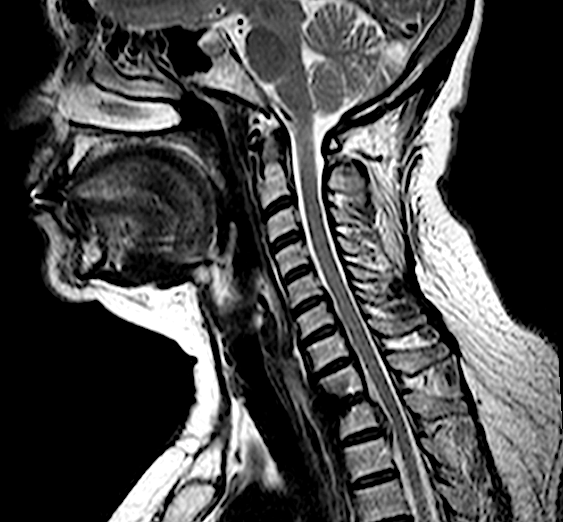

Obsérvese HDTh1-Th2 con migración caudal retrosomática (Th2)

Obsérvese el engrosamiento de LVCP de aspecto calcificado

El compromiso anterior del canal (a pesar de la radiculopatía severa en MSD) me obliga a plantearme un abordaje anterior con posibilidad de ampliar el campo a través de una esternotomía.

T2 6 meses

STIR 6 meses